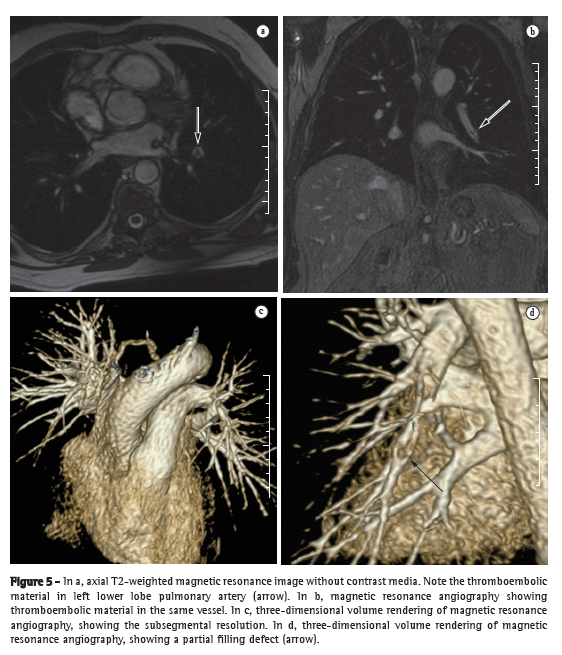

Diagnosis

If a patient suspected of having PH has been screened and signs consistent with increased pressure levels in the pulmonary circulation have been detected in the initial tests, the need to perform RHC to confirm the diagnosis of PH should be evaluated, because a definitive diagnosis of PH can only be established by invasive pressure measurements (Figure 3).

Patients with MPAP ≥ 25 mmHg are diagnosed with PH, and, after the diagnosis has been established, it must be determined whether the PH is precapillary or postcapillary. If the PA occlusion pressure (PAOP) is ≤ 15 mmHg, the PH is classified as precapillary. If the PAOP is > 15 mmHg, the transpulmonary gradient (TPG) must be determined. The TPG is calculated be the difference between the MPAP and the PAOP. When this difference is ≤ 12 mmHg, the increase in the MPAP is considered passive, which means that the increase in the MPAP is caused exclusively by cardiac involvement. If the TPG is > 12 mmHg, the increase in the MPAP is disproportionate to the increase in left ventricular pressure, indicating that there is pulmonary vascular remodeling or another associated cause of increased MPAP (Chart 1 and Figure 3).

The acute test with a vasodilator should be performed during the initial hemodynamic evaluation in patients with precapillary PH. The test can be performed with NO, prostacyclin, or adenosine. The result is considered positive when there is a reduction in the MPAP of ≥ 10 mmHg and when values ≤ 40 mmHg are observed. A positive acute test result predicts the clinical and hemodynamic response to calcium channel blockers.(21,22)

After the presence of PH and its correct hemodynamic classification are confirmed by RHC, various tests should be performed in order to determine the specific etiology of PH. It should be highlighted that idiopathic PH is a differential diagnosis, and it is fundamental to follow an appropriate flowchart to facilitate the diagnostic investigation (Figure 4).